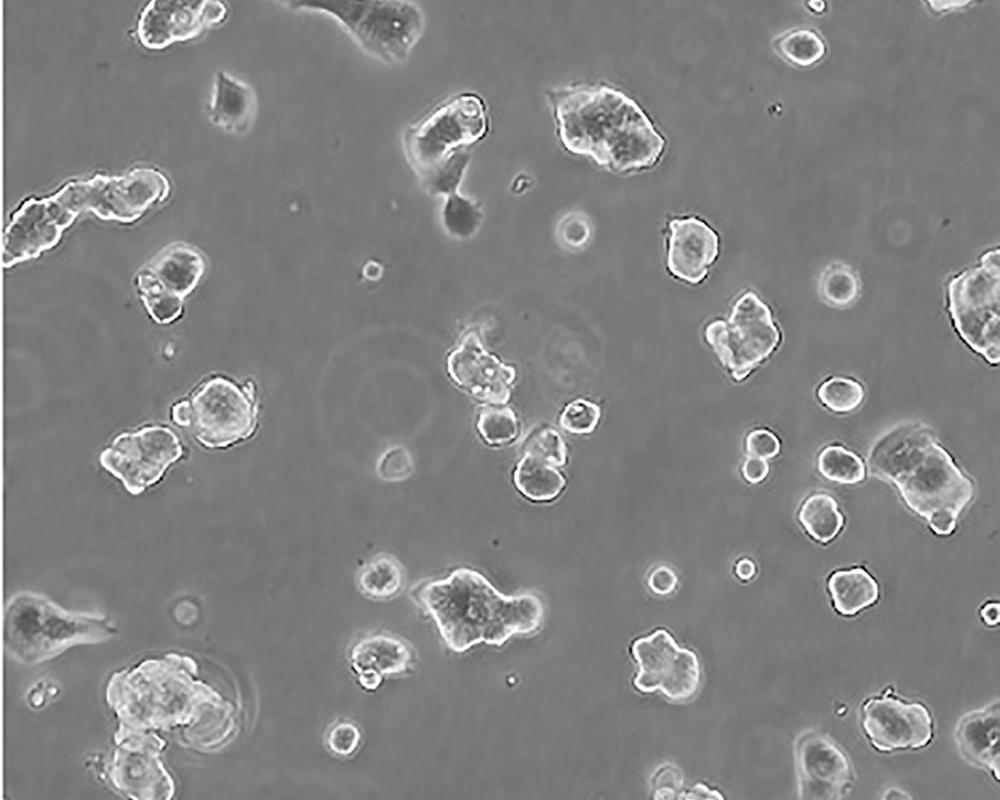

ZR-75-1 [ZR751]

中文名稱 人乳腺癌細胞

組織來源 浸潤性導管癌;腹水轉移;女性

生長特性 adherent

形態特征 epithelial

細胞描述 該細胞產生高水平的黏液素MUC-1 mRNA,低水平的MUC-2 mRNA,但不表達MUC-3基因;表達雌激素受體。